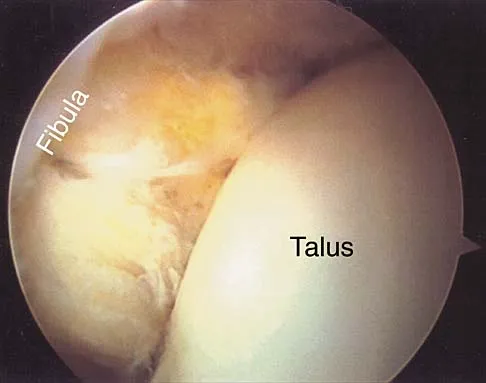

Figures 3a and 3b show the inversion stress radiographs of a patient's ankle. What is the most likely ligament injury pattern?

Figures 5a and 5b show axial and coronal MRI images of the left ankle of a patient with lateral ankle pain. What is the most likely diagnosis?